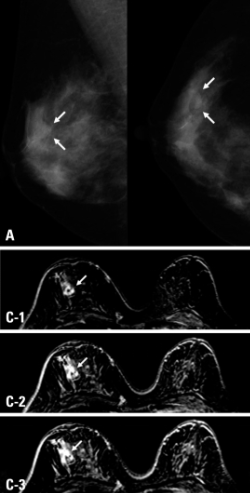

Intraductal papilloma

This condition, also called papillary neoplasm, is a wart-like growth that develops inside a breast duct near the nipple. Usually detected on mammogram, or patient may present with a lump or nipple discharge. It is most common in women aged 35-55. Further testing is required to exclude breast cancer. Single papillomas with no abnormalities do not increase a women’s risk of breast cancer, but those with papillomatosis (multiple papillomas) have a slightly elevated risk. Regular surveillance is advised for this cohort.

Diagnostic value of 3D fast low-angle shot dynamic MRI of breast papillomas. by E. J. Son, E. K. Kim, J. A. Kim, J. Y. Kwak, J. Jeong is licensed under CC BY-NC 3.0